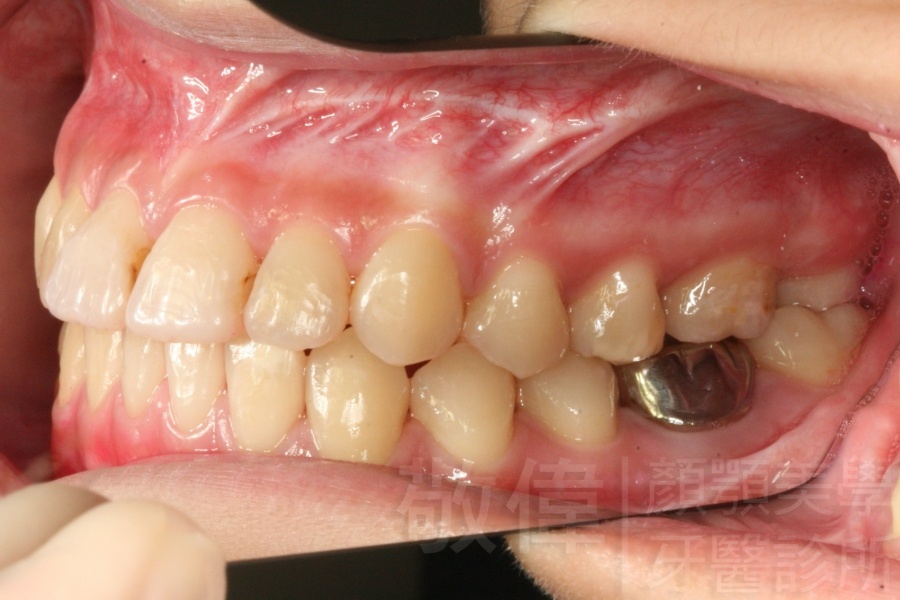

變臉矯正,原來戽斗妹跟大歪臉變成自信正妹

經由本院3D數影X光影像儀分析、與3D齒顎顏矯正技術,再配合口腔顎面正顎專科醫師施以正顎手術治療,雙方共同合作,使患者臉部外觀有很好的改善,大歪變小歪,產生了天南地北的大改變,她的人生也整個變得不一樣。

因為矯正與正顎手術的配合,使「戽斗妹」變成了「陽光正妹」,完全的改變了她的人生,在面對各種場合、與人交際都散發出自信微笑。所以,奉勸家長,如果小朋友有臉顎畸型的問題,應該考慮配合做這種簡單、安全、有效的正顎手術。